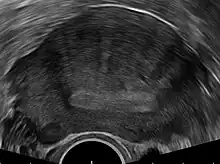

Transvaginal ultrasonography

Transvaginal ultrasonography is a cheap and readily available imaging test that is typically used early during the evaluation of gynecologic symptoms.[24] Ultrasound imaging, like MRI, does not use radiation and is safe for examination of the pelvis and female reproductive organs.[25] Overall, it is estimated that transvaginal ultrasonography has a sensitivity of 79% and specificity of 85% for the detection of adenomyosis.[11]

Common transvaginal ultrasound findings in patients with adenomyosis include the following:[6][26][27]

- globular, enlarged, and/or asymmetric uterus

- abnormally dense or especially varied density within the myometrium

- myometrial cysts - pockets of fluid within the smooth muscle of the uterus

- linear, acoustic shadowing without presence of a uterine fibroid

- echogenic linear striations - bright lines or stripes

- anterior/posterior wall asymmetry

- diffuse spread of small vessels within the myometrium

Less common findings:

- Lack of contour abnormality

- Absence of mass effect

- Ill-defined margins between a normal and abnormal myometrium

The power Doppler or Doppler ultrasonography function can be used during transvaginal ultrasonography to help differentiate adenomyomas from uterine fibroids.[24][28][29] This is because uterine fibroids typically have blood vessels circling the fibroid's capsule. In contrast, adenomyomas are characterized by widespread blood vessels within the lesion.[24] Doppler ultrasonography also serves to differentiate the static fluid within myometrial cysts from flowing blood within vessels.[24]

The junction zone (JZ), or a small distinct hormone-dependent region at the endometrial-myometrial interface, may be assessed by three-dimensional transvaginal ultrasound (3D TVUS) and MRI. Features of adenomyosis are disruption, thickening, enlargement or invasion of the junctional zone.[21]